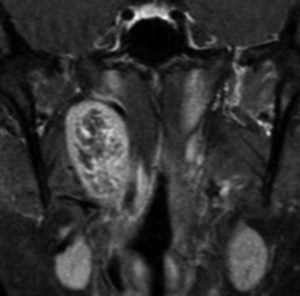

40歳の時に右頸部が腫れているのに気づいて発見され,耳鼻科で生検術され経過をみたものです。7年間の経過観察でかなり増大しました。症状は全くありませんでした。まだ腫瘍増大が止まらないので摘出することにしました。術前は舌咽神経鞘腫と診断することはできません。

手術中に中枢端で舌咽神経本幹に連続性がありここを切断して全摘出しました。それで舌咽神経鞘腫と確定診断ができています。

術後には無症状,他覚的な神経脱落症状はありませんでした。長い間かかって増大したので迷走神経などで代償機能が働いているのだと推定されます。

舌咽神経の末梢枝は,carotid sinusからの感覚神経を含むので,内頸動脈と外頸動脈の間に入り込むように増大することがあります。